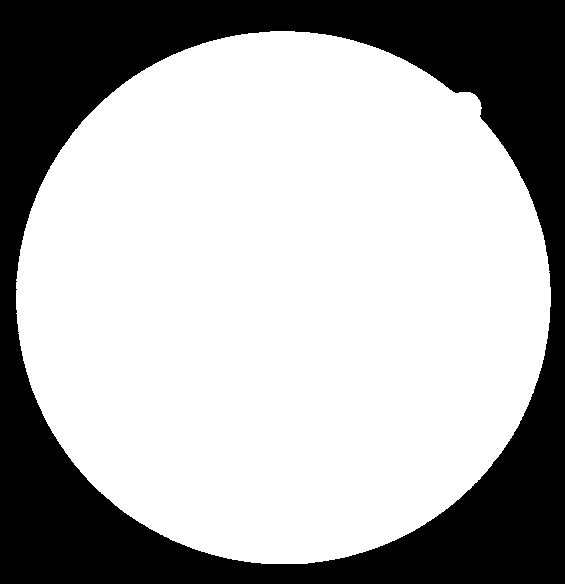

The Digital Retinal Images for Vessel Extraction (DRIVE) data set (Niemeijer et al., 2004) contains 20 training and 20 test entries. Images were captured with a Canon CR5 non-mydriatic 3CCD camera with a 45 degree field of view and cropped to 584565 pixels. Each training entry consists of a retinal image, a binary annotation of vessels (by annotator #1), and a binary mask of the Field of View (FoV) indicating the useful image content. The FoV masks cover 69% of the rectangular images. Each test entry includes an additional manual segmentation by annotator #2, enabling the evaluation of human annotators as a baseline. A complete entry from the test set is visualized in Figure 1.

Even this handful of quotations suggests that some authors evaluate performance only in the area covered by the FoV mask, while others use all pixels of the images. The pixels outside the FoV are usually non-vessel pixels accounting for about 31% of all pixels in the images. If they are treated as true negatives, the accuracy and specificity increases tremendously. To illustrate the magnitude of this effect, we evaluate the segmentation of annotator #2 against annotation #1 (as ground truth) under the FoV mask and including all pixels of the images. With the FoV mask, , and , but using all pixels, , and . Omitting the FoV mask increased the and values by more than % and , respectively. The slight change in sensitivity is due to an average of 15 vessel pixels in the annotations #1 being outside the FoV. Since many authors report 0.1% improvements in accuracy, the variation in the region used for evaluation can cause an enormous bias when algorithms are compared and ranked.